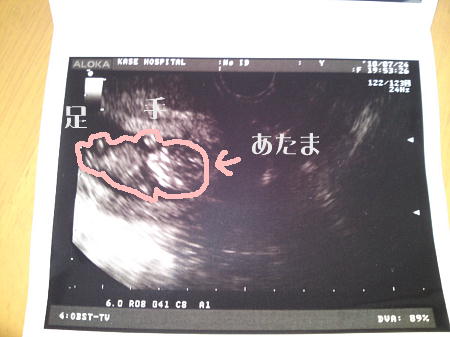

昨日のエコー写真です。

赤ちゃんの形がはっきりわかります。

キューピーちゃんみたい。

エコーで見てもらうと、お腹の赤ちゃんは無事でした。

ちゃんと心臓がぴょこぴょこ動いているのも、頭や足を動かす姿も見えました。